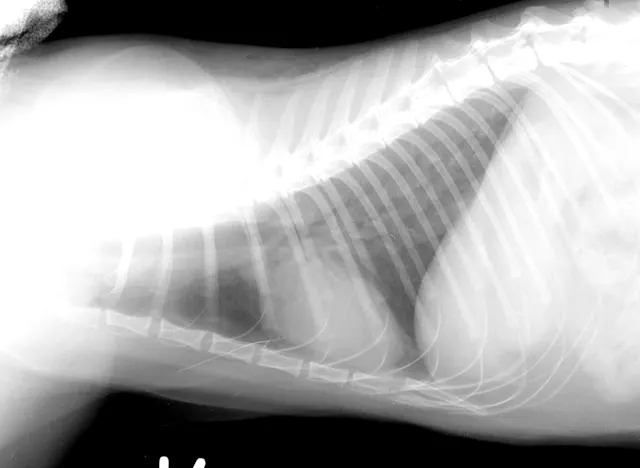

In addition to serologic tests, thoracic radiography and cardiac ultrasonography are important diagnostic tests in feline heartworm infection.

The cardiac silhouette of a cat with heartworms rarely has the "inverse D" appearance, or main pulmonary artery bulge, as seen in dogs. Cats more typically demonstrate radiographic findings compatible with feline bronchial disease ("asthma"). Nevertheless, certain findings, such as a caudal lobar pulmonary artery larger than 1.6 times the ninth rib at the ninth intercostal space, are quite suggestive of heartworm disease.

FIGURE 1A

Lateral thoracic radiograph from a cat with heartworm disease. A fine interstitial pattern is noted in the caudal lung lobes, and the chest is somewhat hyperinflated. This radiographic pattern is similar to, and thus can be confused with, that of feline bronchial disease.